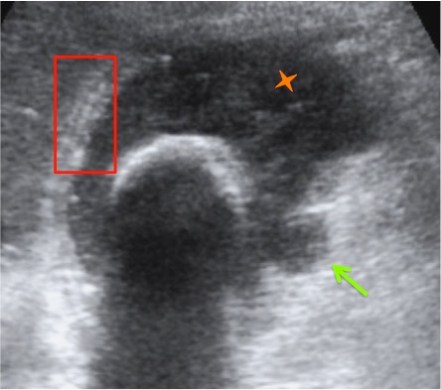

Se realiza ecografía abdominal:

Con estos hallazgos ecográficos podemos concluir que el paciente presenta una COLECISTITIS AGUDA.

Criterios ecográficos de colecistitis (No existe consenso generalizado):

– Murphy ecográfico positivo y colelitiasis: es la combinación de signos ecográficos más predictiva de colecistitis aguda (VPP 92%). Puede resultar difícil observa la litiasis si ésta se localiza en el conducto cístico o en el cuello de la vesícula. Con engrosamiento mural el VPP aumenta al 94%)

– Otros signos secundarios son:

- Engrosamiento de la pared vesicular (>4mm) en ausencia de enfermedad hepática crónica, ascitis o insuficiencia cardiaca (el VPP asciende al 94%).

- Líquido perivesicular.

- Imágen de triple pared con capa hipoecoica central.

- Vesícula biliar distendida.